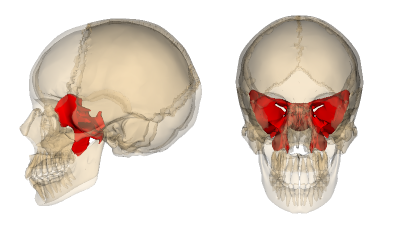

The sphenoid bone is one of those parts of your skull most people never think about, but it actually plays a huge role in how symmetrical your face looks. It sits deep behind your eyes and between your temples, acting like a keystone that holds a lot of your facial structure in place. Its shape and position affect not just your eye placement and orbital depth, but also the alignment of your cheekbones, jaw, and even your forehead.

The sphenoid is right behind your eyes, at the center of the skull base. The greater wings help form the sides of your eye sockets and your temples, while the lesser wings are part of the roof of your orbits. There’s also a little depression called the sella turcica that holds the pituitary gland.

It connects to the frontal, zygomatic, maxilla, ethmoid, and temporal bones, which is why it’s considered a keystone for your midface. Basically, it supports a lot of what people subconsciously notice when they look at your face.